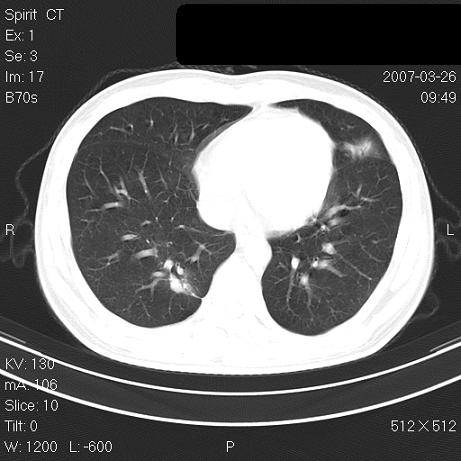

标题: CT7171B:补充治疗后2周复查 [打印本页]

标题: CT7171B:补充治疗后2周复查

治疗后2周复查,请讨论

结合以前的ct片,还是考虑肺挫伤,吸收多了。

支持:创伤性湿肺。现肺挫裂伤(出血 积气)大部分吸收。建议继续治疗!

结合以前的ct片,支持创伤性湿肺。现大部分吸收。

支持:创伤性湿肺、肺挫裂伤。现肺挫裂伤(出血、渗出、液气腔)大部分吸收。建议继续治疗!

支持:创伤性湿肺、肺挫裂伤。现肺挫裂伤(出血、渗出、液气腔)大部分吸收.

结合老片支持创伤性湿肺、肺挫裂伤。

经治疗后病灶明显吸收,考虑创伤性湿肺、肺挫裂伤